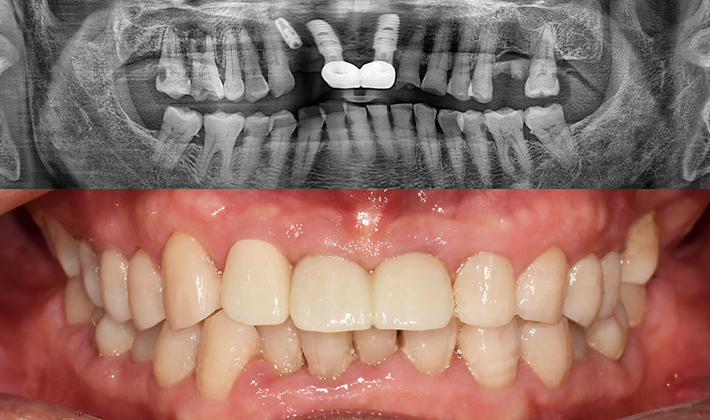

치과가 무서워 10년 동안 미뤄온 임플란트 수술 그 결과는?

2026.01.21